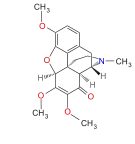

Oripavine derivatives

Thienorphine

- 7-PET

- Acetorphine

- Alletorphine (N-allyl-noretorphine)

- BU-48

- Buprenorphine

- Buprenorphine-3-glucuronide

- Cyprenorphine

- Dihydroetorphine

- Etorphine

- Homprenorphine

- 18,19-Dehydrobuprenorphine (HS-599)

- N-cyclopropylmethylnoretorphine

- Nepenthone

- Norbuprenorphine

- Norbuprenorphine-3-glucuronide

- Thevinone

- Thienorphine

Structures

| Oripavine derivatives | ||||

|---|---|---|---|---|

7-PET 7-PET |

Acetorphine Acetorphine |

Alletorphine Alletorphine |

BU-48 BU-48 |

Buprenorphine Buprenorphine |

Cyprenorphine Cyprenorphine |

Dihydroetorphine Dihydroetorphine |

Etorphine Etorphine |

Homprenorphine Homprenorphine |

18,19-Dehydrobuprenorphine 18,19-Dehydrobuprenorphine |

N-cyclopropylmethylnoretorphine N-cyclopropylmethylnoretorphine |

Nepenthone Nepenthone |

Norbuprenorphine Norbuprenorphine |

Thevinone Thevinone |

Thienorphine Thienorphine |